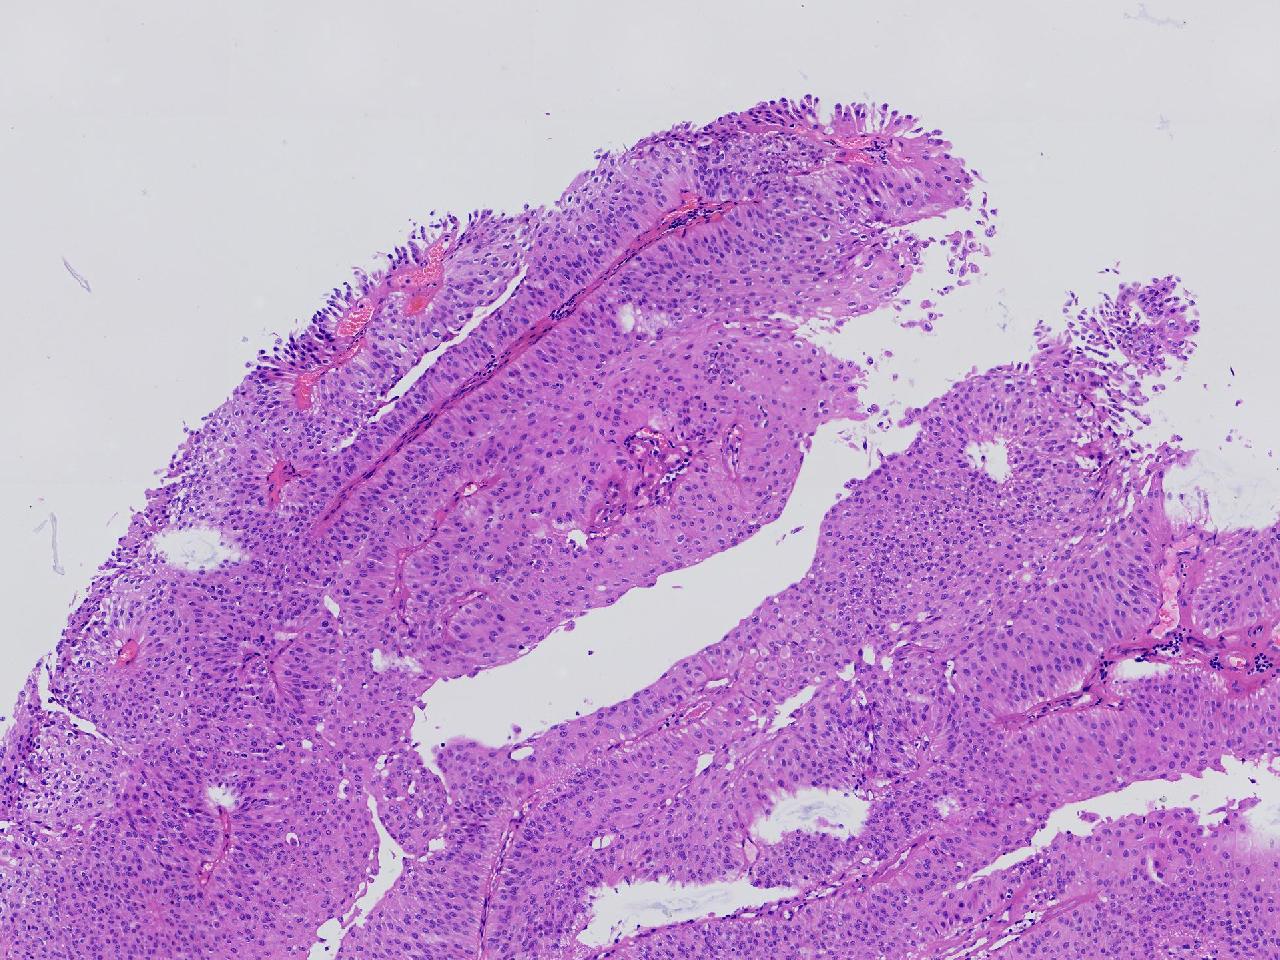

男,79岁,膀胱肿物。

膀胱肿物

灰白色不整形软组织多块,2X1X1厘米。

考虑:乳头状尿路上皮癌

考虑低级别,非浸润。

乳头状尿路上皮癌,低级别。

这几张图片上没有看到明确的浸润。